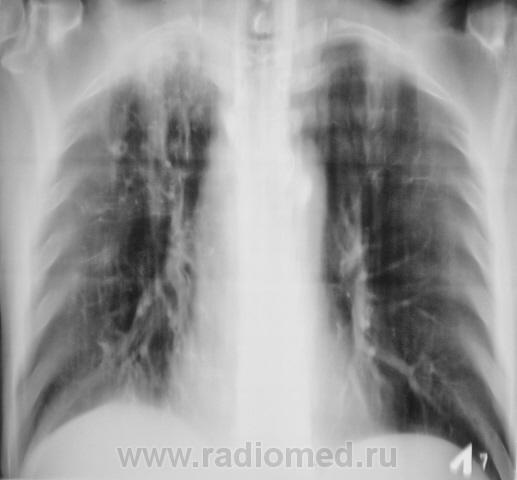

диссемин tbs, прав плеврит?

ИМХО:Справа в верхнем поле плотные туб.очаги; справа в нижем поле на фоне деформированного лёгочного рисунка, мелкие диссеминироанные тени, что в совокупности, предварительно можно расценить, как подозрение на проявление ракового канцероматоза. Для уточнения рекомендована КТ грудной клетки. А какое заключение вынесли фтизиатры?

Забрали к себе. МТБ +

Динамика на фоне лечения здесь будет хорошей тактикой. А как насчет выпота справа?

Вот этот пациент через 3 месяца после специфического лечения.

Да, это снимки через 3 месяца, диагноз на ЦВК утвержден.

МБТ выявлены неоднократно, в том числе и методом посева. Пациент продолжает получать "специфическое" лечение.